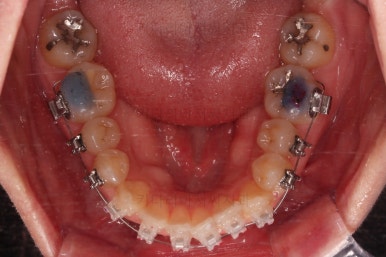

초진 시, 입안의 모습입니다.

좌측 송곳니가 덧니처럼 튀어나가 있고, 송곳니 옆의 작은 억므니가 안으로 쏙 들어가서 덧니 느낌이 더 강조되어 보이네요.

위아래 앞니가 긴밀하게 겹침이 없는 약간의 개방교합(오픈바이트, Openbite) 경향이 보입니다.

개방교합을 개선하면서 교합을 맞춰주고요.

디테일한 중앙선이라던지, 안에서 끄집어낸 치아의 각도라던지 비롯해서 환자분이 원하시는 느낌을 반영해서 마무리를 합니다.